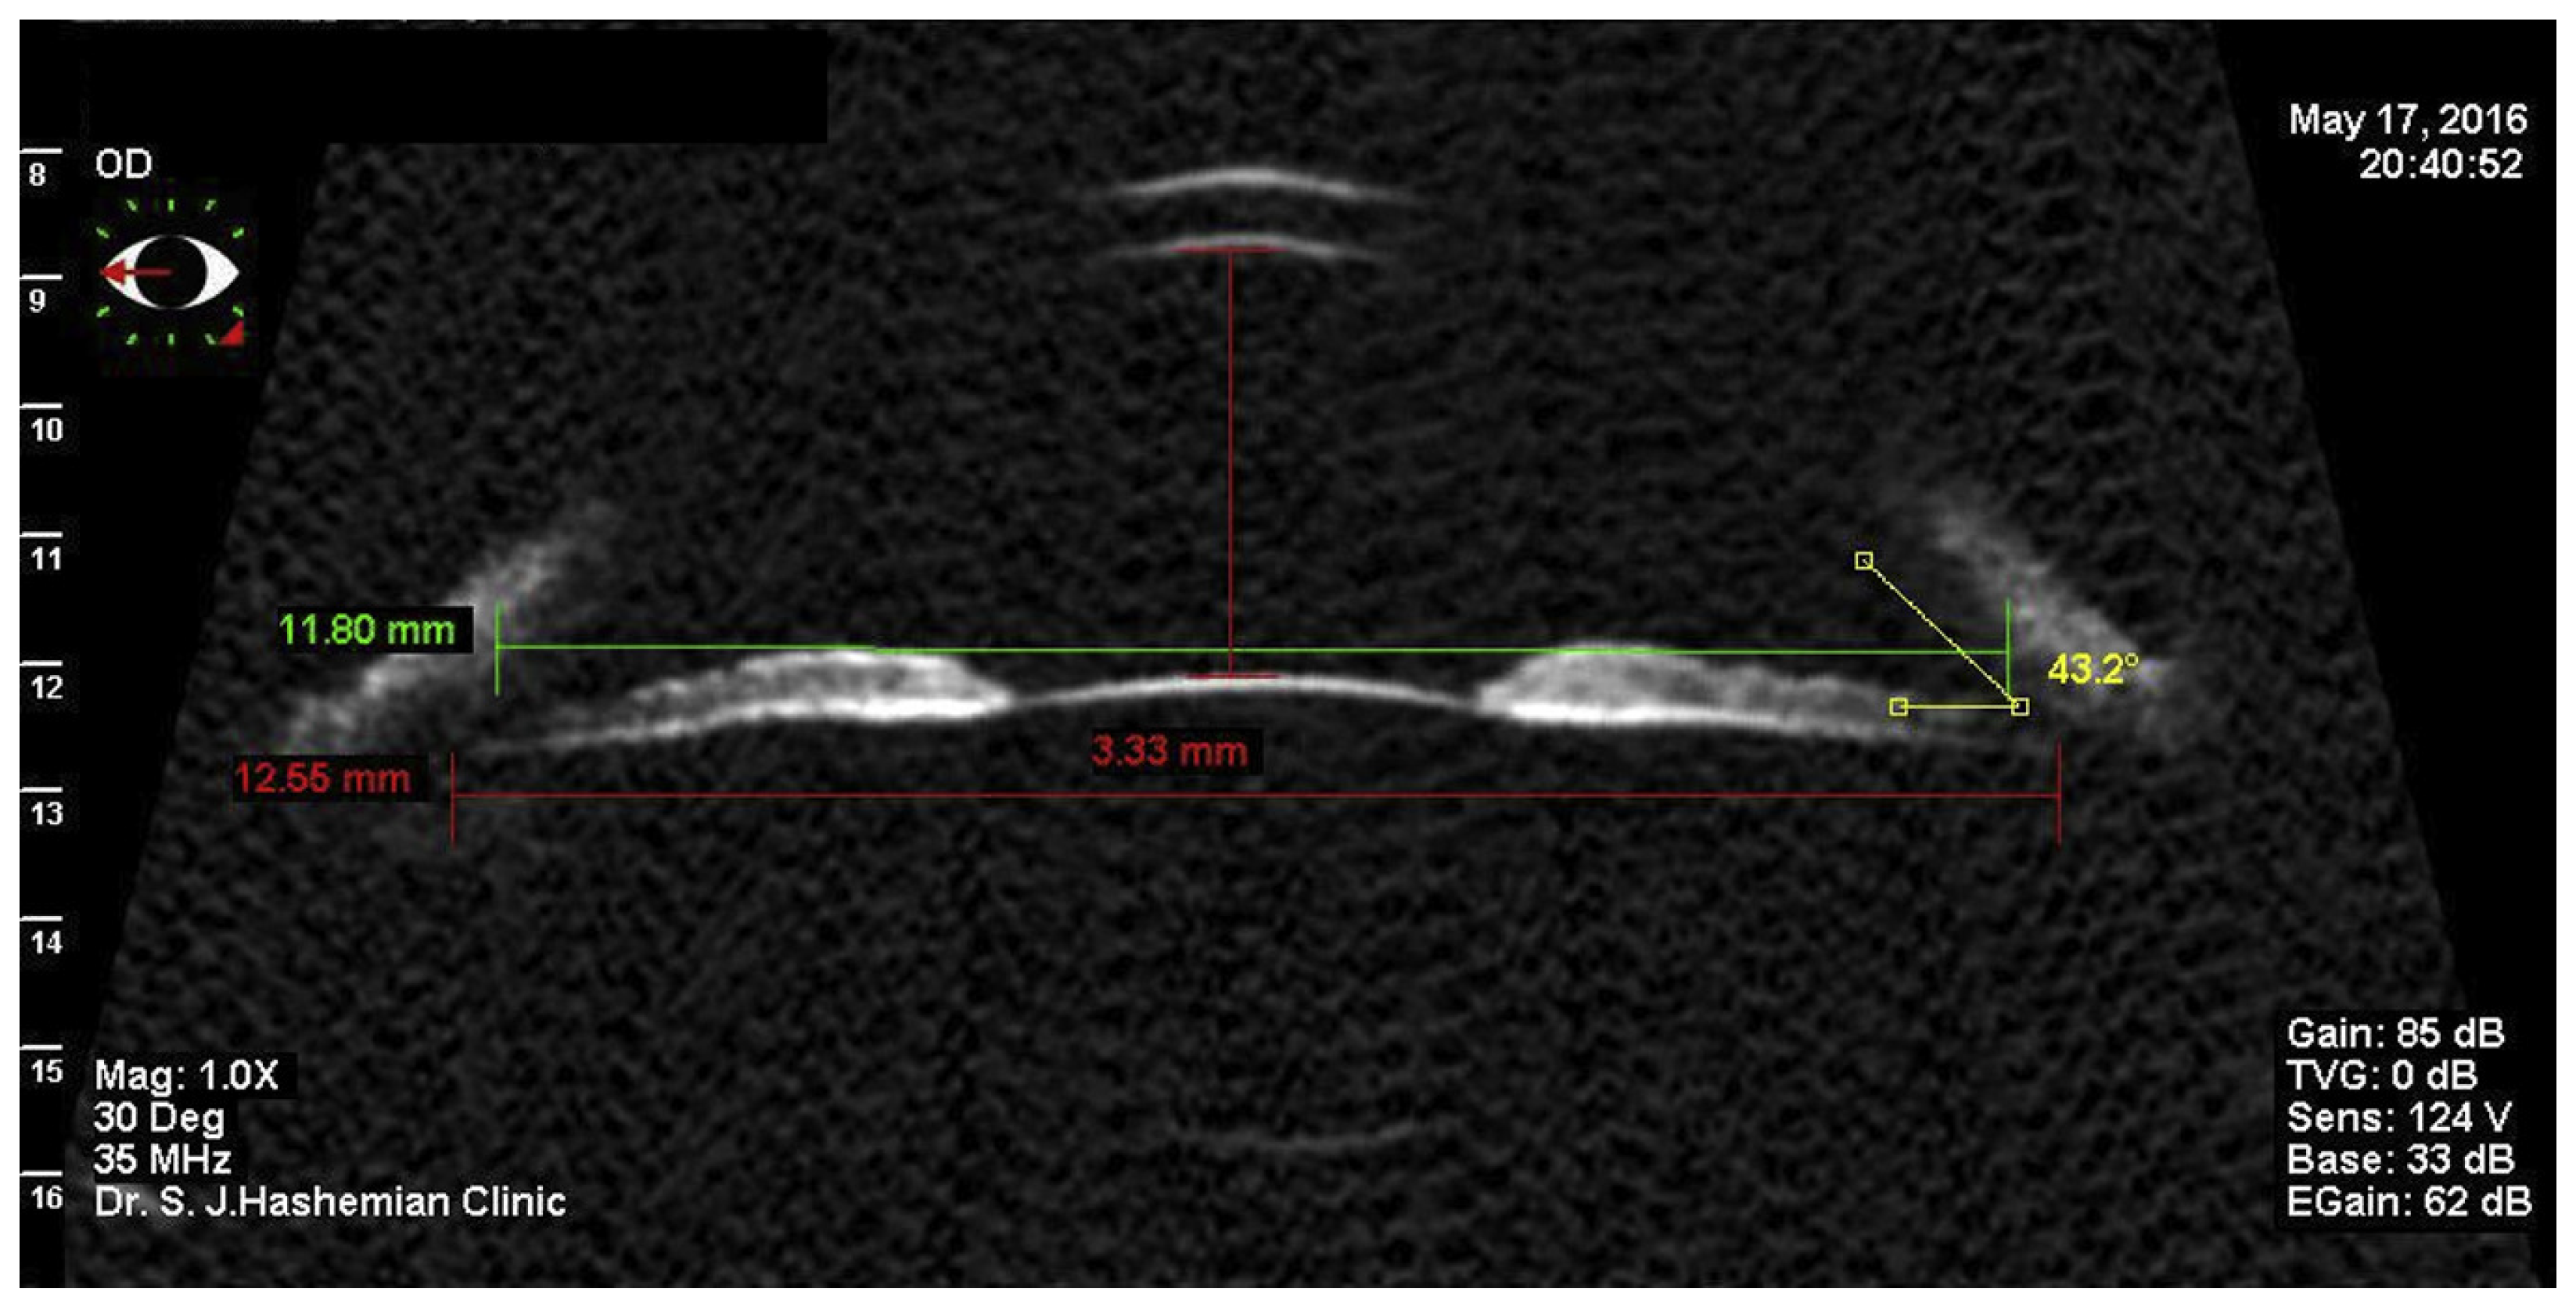

- Kim, K.H.; Shin, H.H.; Kim, H.M.; Song, J.S. Correlation between ciliary sulcus diameter measured by 35 MHz ultrasound biomicroscopy and other ocular measurements. J. Cataract. Refract. Surg. 2008, 34, 632–637. [Google Scholar] [CrossRef]

- Hashemian, S.J.; Mohebbi, M.; Yaseri, M.; Jafari, M.E.; Nabili, S.; Hashemian, S.M.; Hashemian, M.S. Adjustment formulae to improve the correlation of white-to-white measurement with direct measurement of the ciliary sulcus diameter by ultrasound biomicroscopy. J. Curr. Ophthalmol. 2018, 30, 217–222. [Google Scholar] [CrossRef]